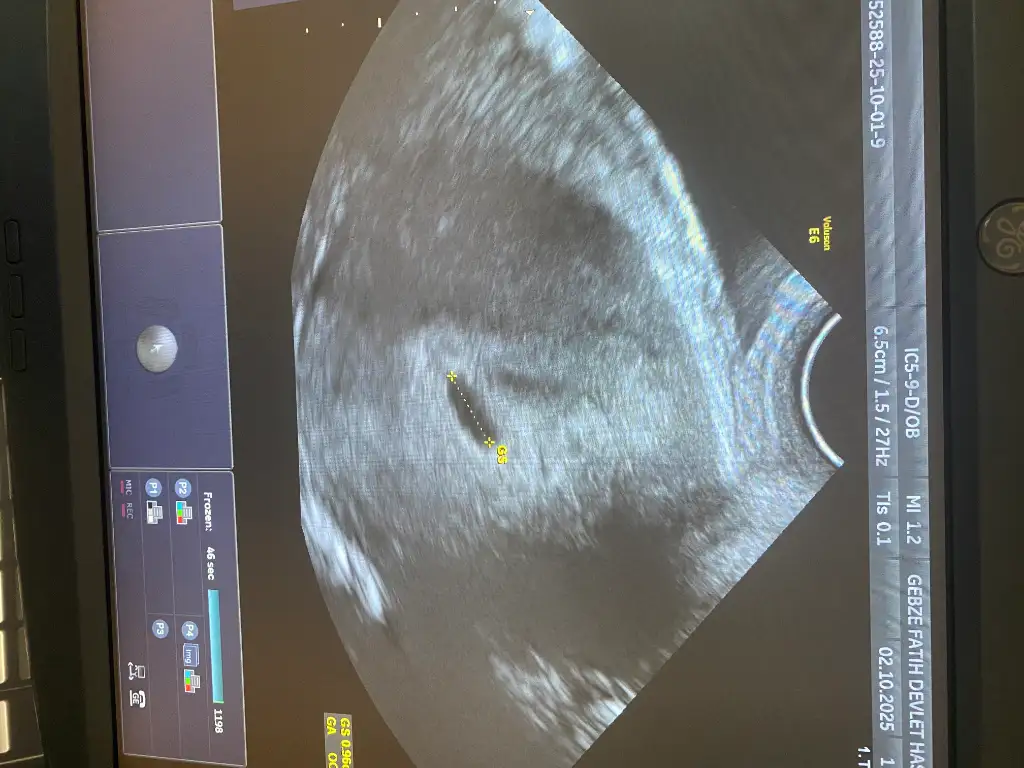

İnşallah bu carsmaba gününün ultrason kağıdı bu gününkini almayı unuttum ama buna göre bariz büyümüştüİnsallah dolar kesemizin ici ben pazartesi tekrar gidicem senin hic usg foton var mı atar mısın

Benimkimde dün böyleydiİnşallah bu carsmaba gününün ultrason kağıdı bu gününkini almayı unuttum ama buna göre bariz büyümüştü

Şekli için bişey dediler miBenimkimde dün böyleydi

Yok niye kiŞekli için bişey dediler mi

Benimkimde dün böyley

Benimki bariz yuvarlak ya farklı olması normal midir diye düşündümYok niye ki

valla bilmiyorum kiBenimki bariz yuvarlak ya farklı olması normal midir diye düşündüm